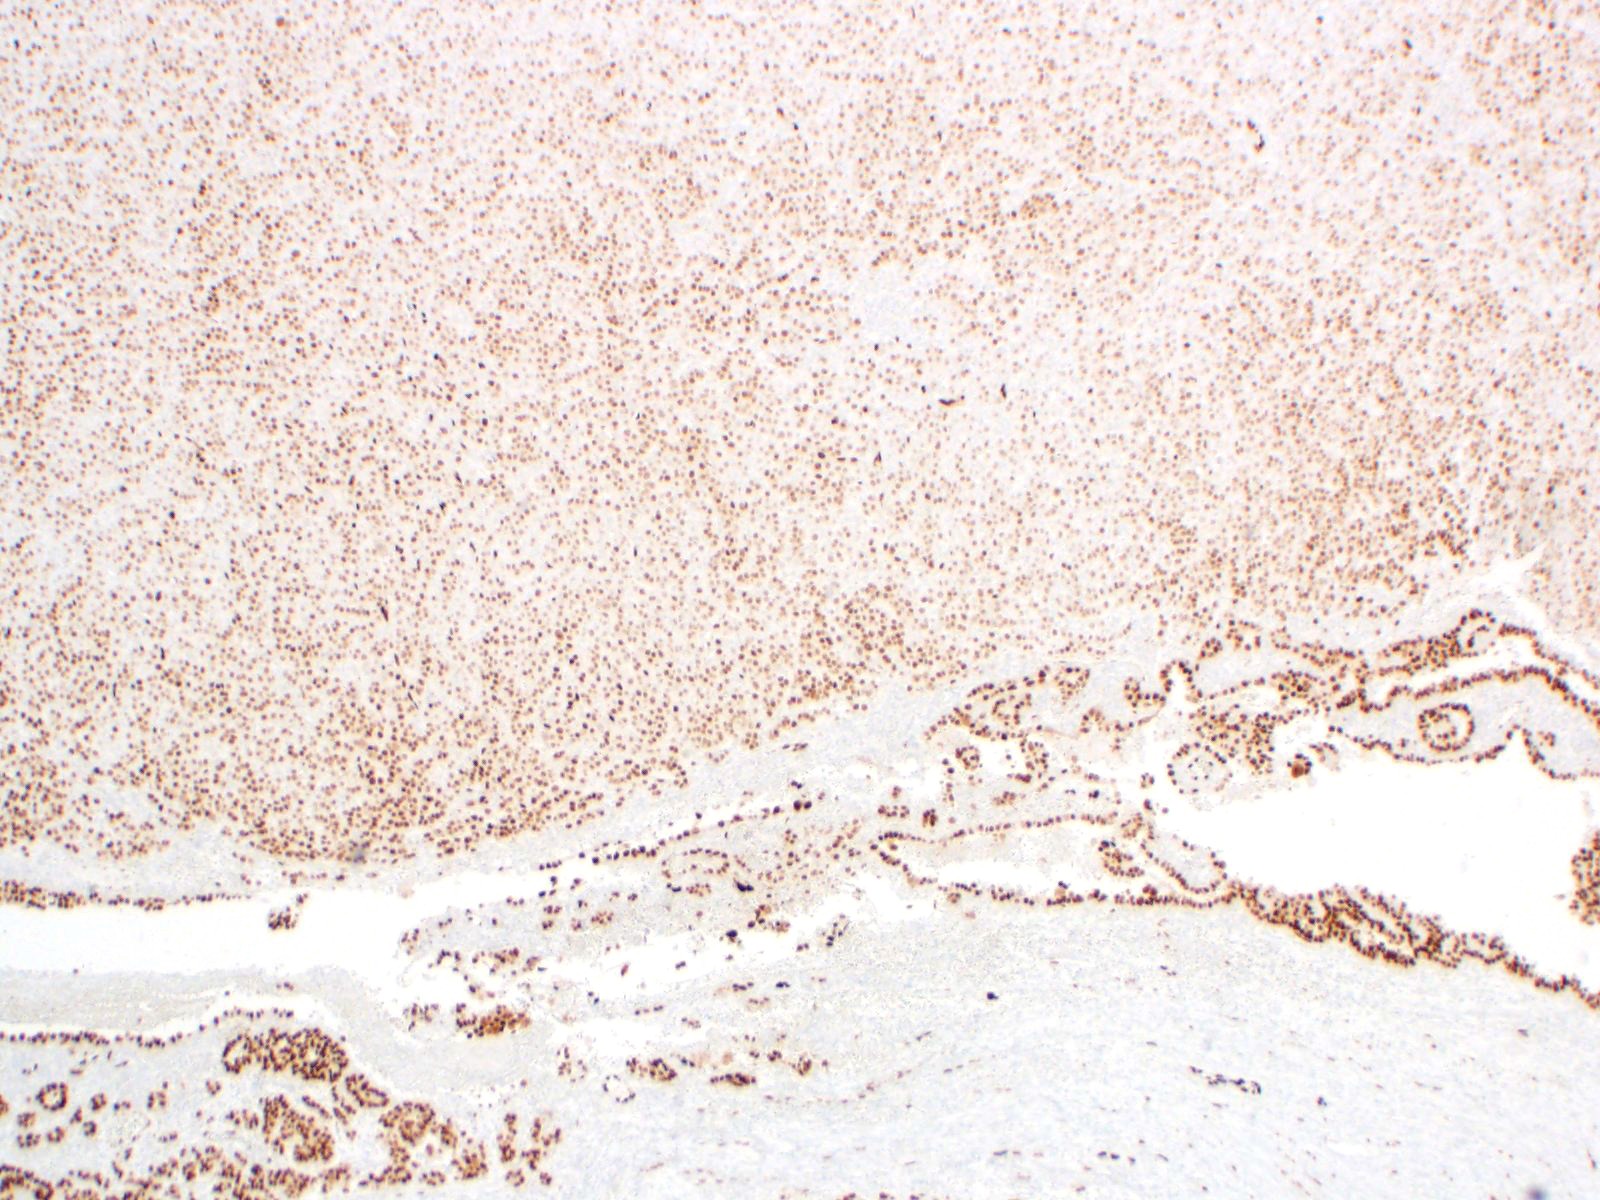

| 2SC |

S-(2-succino)-cysteine |

Rabbit polyclonal (Cambridge Research Biochemicals)

Hereditary leiomyomatosis and renal cell carcinoma (HLRCC) syndrome-associated RCC and leiomyoma

Most renal tumors and leiomyomas not associated with HLRCC

Staining Pattern

Cytoplasmic and nuclear

| HLRCC-associated RCC |